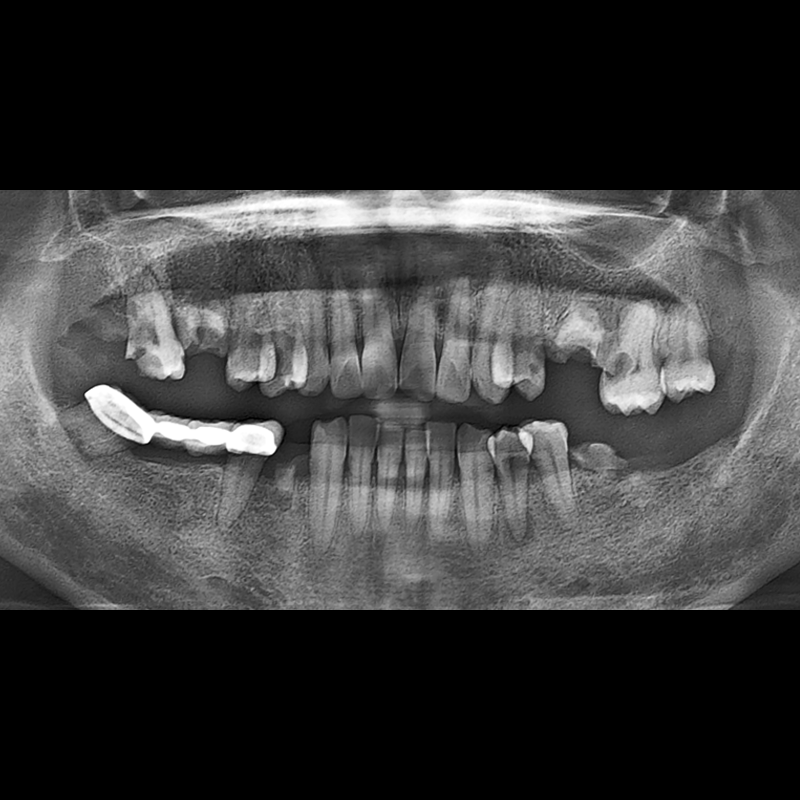

BEFORE AFTER

种植牙前后的照片 2025.12.10

在缺失的牙齿部分和难以挽救的牙齿位置植入了种植牙。